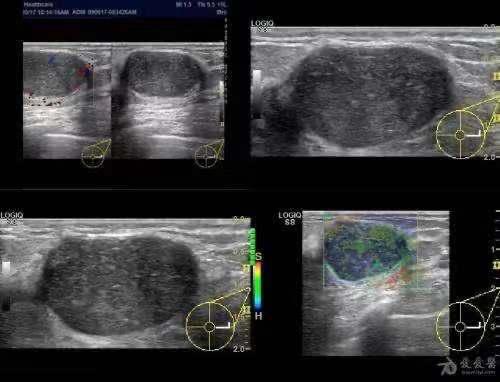

- 纖維囊腫在超音波影像上呈現為一顆有明確邊界的腫塊,腫塊壁薄且均勻。

- 內容物呈無回音的均質黑色,代表液體性質。

- 腫塊後方常見有強烈的聲音增強(亮白回音),這是液體囊腫典型的聲學特徵。

- 若符合上述條件,通常可診斷為良性纖維囊腫,不需立即介入治療,只需定期追蹤。